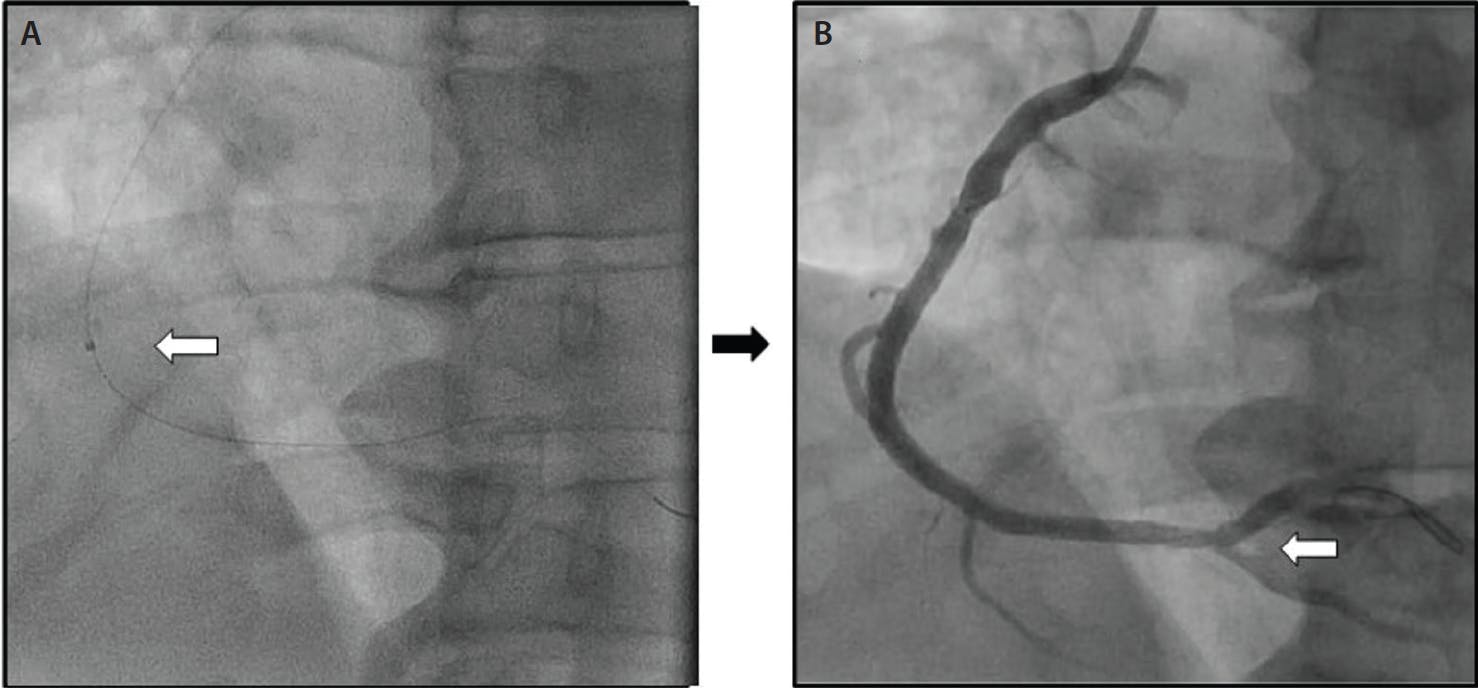

INTERVENTION

Upon arrival to the cardiac catheterization laboratory, transradial arterial access was obtained, and a 6-F Glidesheath Slender Sheath® (Terumo Interventional Systems) was introduced into the right radial artery. A 5-F Tiger catheter (Terumo Interventional Systems) was used to engage and image the left and right coronary arteries. Coronary angiography demonstrated nonobstructive coronary artery disease in the left coronary arteries with a 100% acute thrombotic occlusion at the mid segment of the RCA (Figure 1). At this point, intravenous cangrelor was initiated and the RCA was easily wired using a Runthrough NS Extra Floppy® wire (Terumo Interventional Systems). After predilating with a 2.0- X 10-mm semicompliant balloon, extensive thrombus was visualized on angiography with restoration of only TIMI 1 flow. At this point, given the presence of significant thrombus burden throughout the RCA and persistent chest pain, the decision was made to perform mechanical power aspiration using the Indigo System CAT RX. Two passes were made, aspirating a total of 40 mL of blood with extensive thrombus (Figure 2). There was a significant improvement in flow, distally limited by the presence of a small, persistent, distal RCA thrombus. Two drug-eluting stents (DESs; 3.5- X 38-mm) were placed followed by proximal postdilatation with a 4.0- X 15-mm noncompliant balloon. Final angiography and intravascular ultrasound demonstrated excellent stent expansion and apposition, resulting in restoration of TIMI 3 flow to the distal RCA. The patient remained hemodynamically stable with resolution of his chest pain. Radial arterial hemostasis was achieved using a TR Band® (Terumo Interventional Systems). The patient was discharged 2 days later.

DISCUSSION